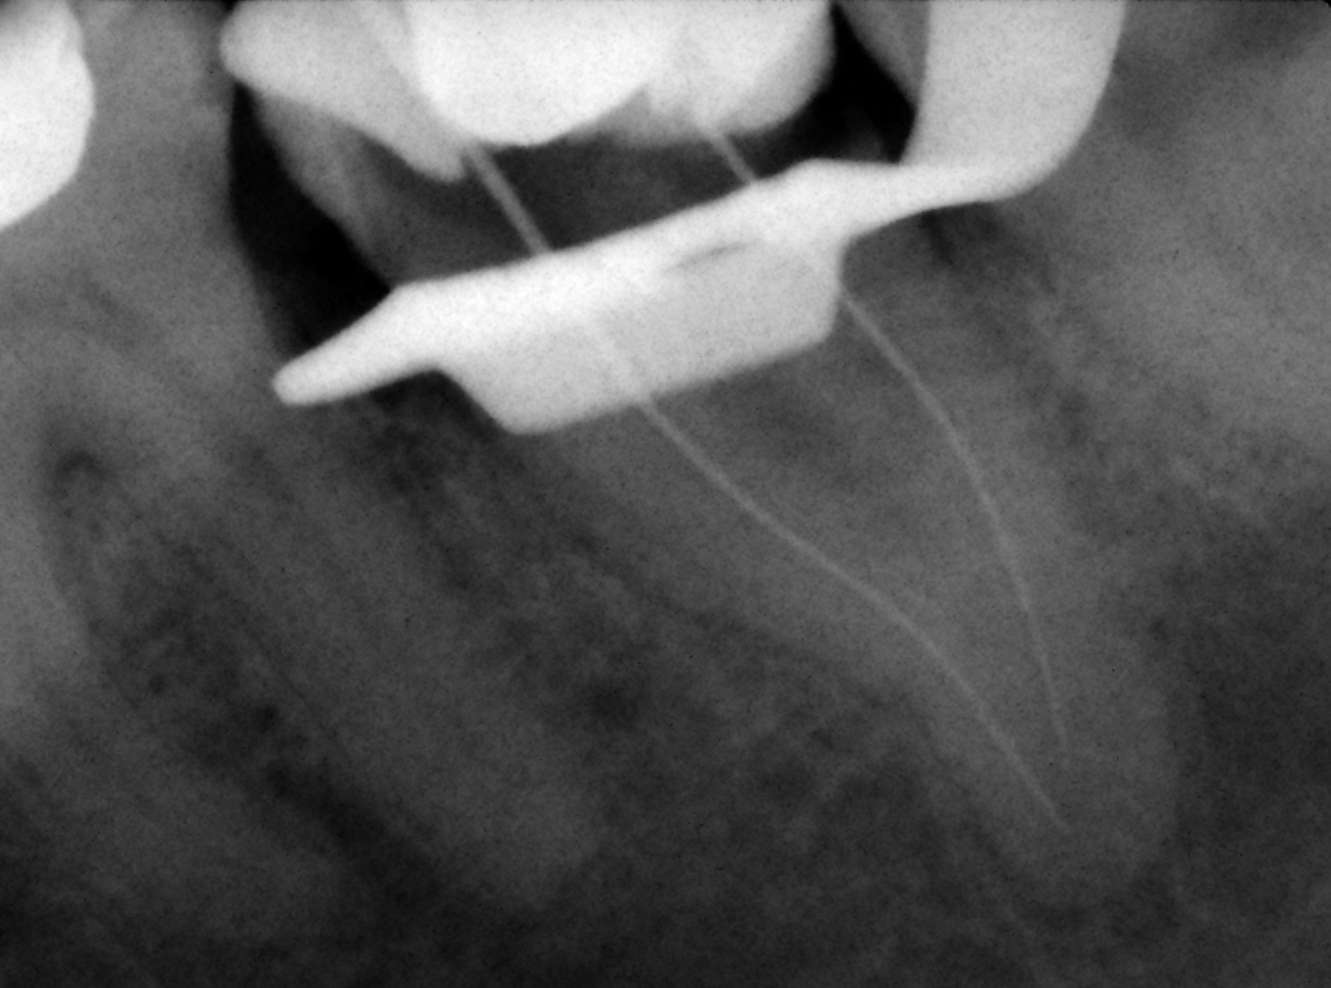

Caso clínico Master: BIOPULPECTOMÍA 37 -Tipo IV o Istmo-

Durante la instrumentación comprobé que no

estábamos ante una clasificación tipo IV de Vertucci, al medir ambos conductos

la lima bajaba a su respectiva LT.

En la obturación comprobé que se trataba de un

Istmo en la parte apical con salida lateral.